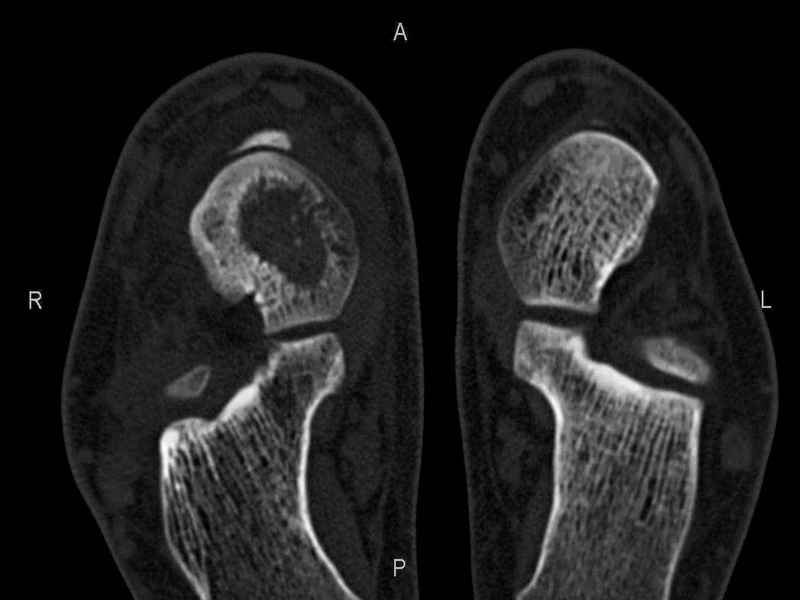

Уважаемые коллеги, обратился за помощью пациент, мужчина, 25 лет. С жалобами на болевой синдром в области голеностопного сустава и среднем отделе стопы. Травму отрицает. Со слов, болевой синдром в течении 1 года. Последние 1-1.5 мес периодически вынужден пользоваться костылями. После ограничения нагрузки боли уменьшаются.Соматически здоров. До появления болей активно занимался рукопашным боем. На СКТ картина рассекающего остеохондрита блока таранной кости, киста шейки таранной кости с признаками импрессии суставной поверхности. А также - разрастания переднего края б\берцовой кости сопровождающиеся клиникой импиджмент синдрома. Предполагаемый план лечения- удаление свободного фрагмента суставного хряща из трансмаллеолярного доступа с рассверливанием поверхности дефекта, кюретаж кисты шейки с заполнением полости биокомпозитом + дебридмент переднего отдела голеностопного сустава. Прошу высказать своё мнение, за и против, предполагаемого плана лечения. А также по возможности ответить на вопросы: 1. Есть ли необходимость в улучшении васкуляризации таранной кости (например подтаранный артродез). 2. Учитывая планируемое применение биокомпозитного цемента целесообразно ли заполнение им дефекта блока таранной кости с моделированием края суставной поверхности.

СТ чётко демонстрирует секвестр, но открыв сустав вероятно, что хрящ тарана окажется интактным и только пальпацией/ ЭОП можно будет

идентифицировать локализацию секвестра. Если вы с этим столкнетесь, то секвестрэктомию я бы предложил сделать не со стороны суставной поверхности тарана, а со стороны угла тарана, субхондрально кюрретаж стенок, разнонаправленную туннелизацию спицей или 1.1мм сверлом и заполнить дефект спонгиозным графтом.